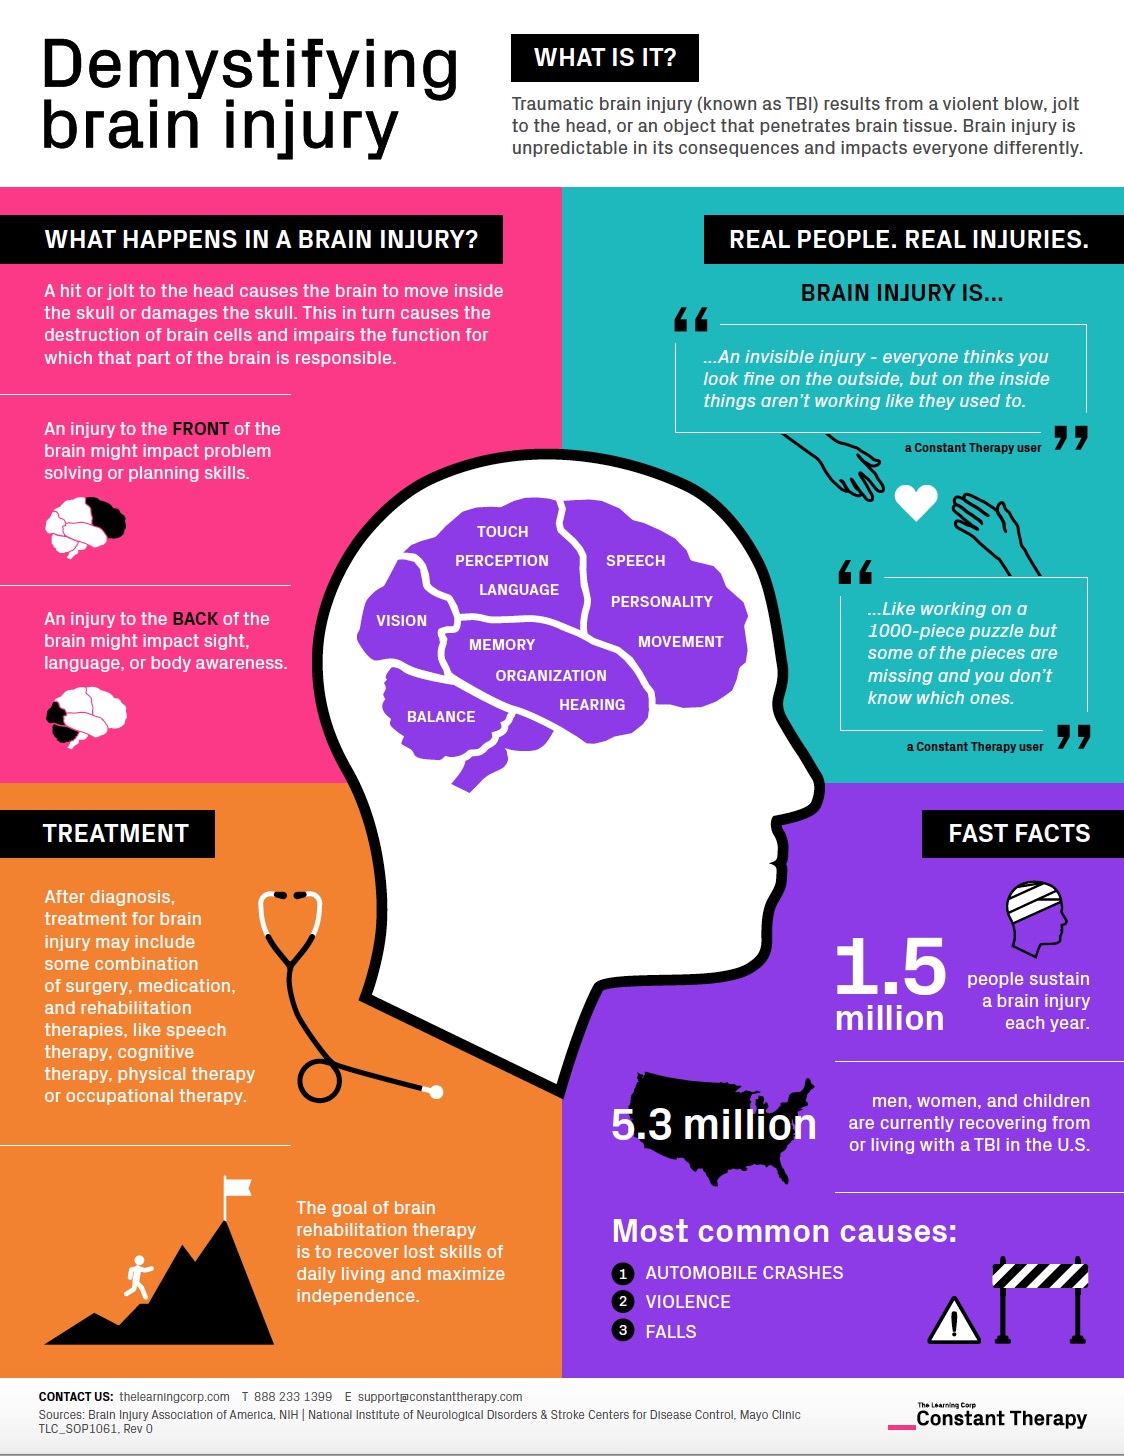

Demystifying Brain Injury Infographic Explains The Basics Constant

https://thelearningcorp.com/wp-content/uploads/2019/03/DemystifyingBrainInjury.jpg